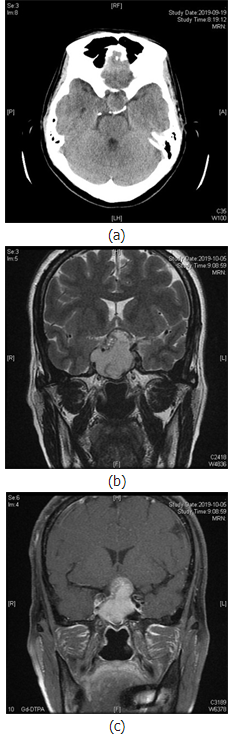

内分泌实验室检查未见明显异常,行颅脑CT示:蝶鞍扩大,鞍底下陷,鞍区及鞍上见团块状稍低密度影,边界欠清(见图1(a));鞍区MR动态增强示:蝶鞍扩大,鞍底下陷,鞍内及鞍上可见不规则短T1长T2信号,信号欠均匀(见图1(c)~(f));动态增强扫描边缘可见延迟强化,大小约41mm×38mm×25mm,边界清晰,视交叉受压上抬,移位,垂体柄显示不清,右侧海绵窦受累(图1(b)),考虑垂体瘤卒中。

图1.患者影像学检查资料。图1(a)示CT扫描下鞍区占位中存在低密度赢;图1(b)示鞍区平扫T2相鞍区占位内长短不一信号;图1(c)示增强磁共振扫描中鞍区占位内不均一信号;图1(a)~(c)均示垂体瘤内部有异常液体存在;图1(d)~(f)鞍区

但CT对急性期出血的确诊率高,且在显示骨质改变方面较MRI强。本例患者中可见患者颅内CT瘤体中存在明显的低密度影,而在MRI检查可发现患者T2相瘤体内部存在长信号影,考虑是患者瘤体内有出血,而患者增强MRI检查发现患者瘤体内部存在长短不一信号影,但是考虑患者肿瘤形态,患者卒中类型仅分类为不规则型,患者术中内镜观察肿瘤呈灰红色,切除过程中也发现血块,这一特点证实了患者垂体瘤卒中的诊断。